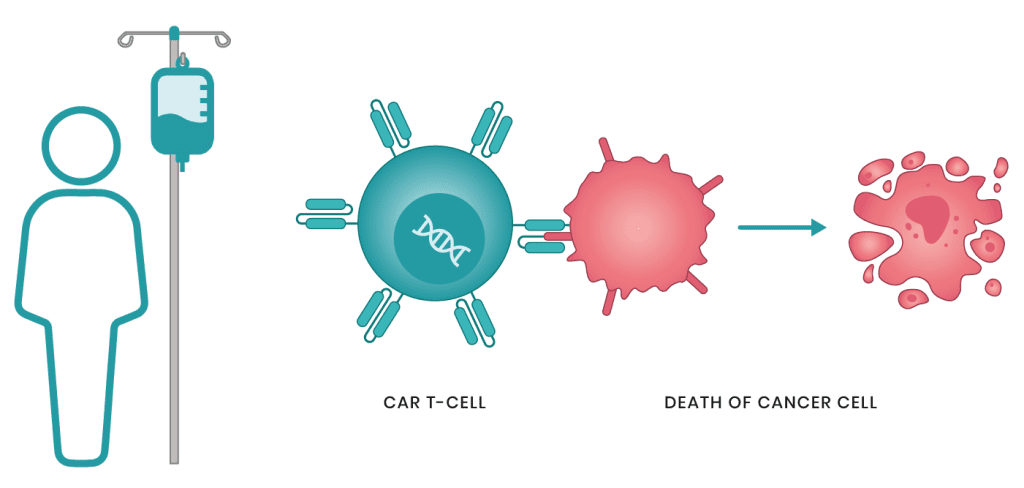

أطباء الأورام والسرطان

50 listings